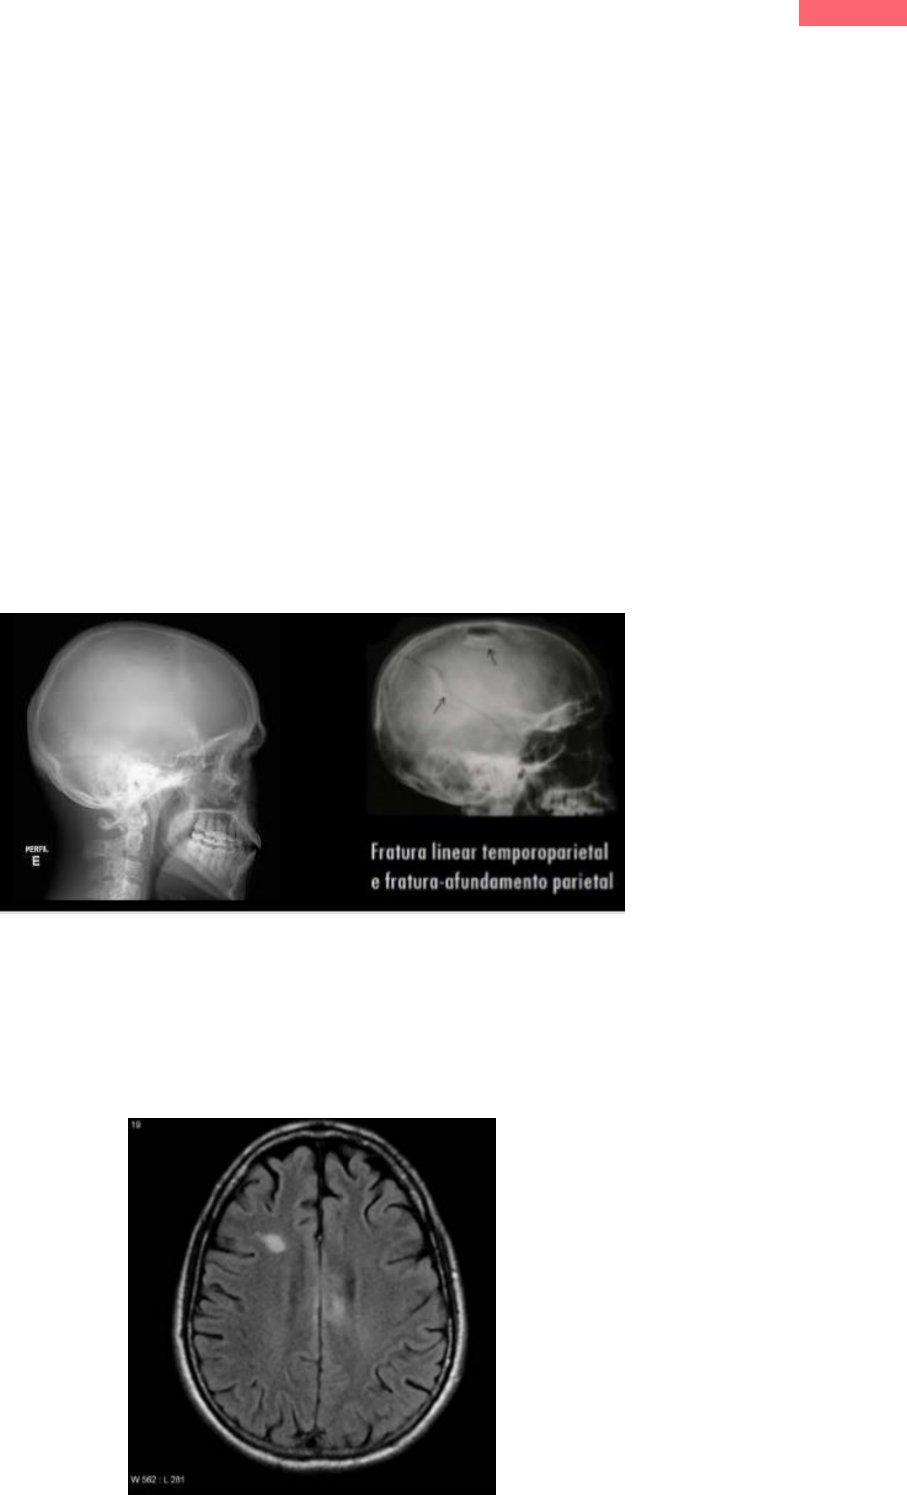

Imagem 1: região parietal direita; imagem 2: região temporo-pariental direita.

Fratura com afundamento

 Aspecto de “Pingue-pongue” no RN, mas também ocorre

no adulto;

 Fratura que não permanece alinhada com os fragmentos

ósseos adjacentes;